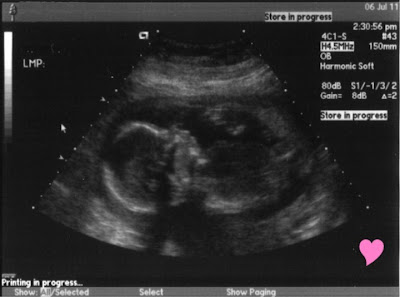

We have made it to 20 weeks!

On July 6th we had our 20 week sonogram to make sure our little miracle was growing ok. We found out that everything was growing normal and at the right speed. We also found out that we are having a Girl. She is very active. She was moving so much during the sonogram. It was so much fun to watch her. She had her feet on her shoulders for most of the sonogram and her little hands and feet were going like crazy.

We love you Baby W!!!